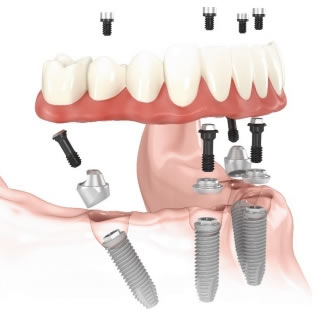

Desenho esquemático da arcada inferior com implantes para receber uma prótese fixa aparafusada.

Realizando de 4 a 8 implantes é possível adaptar com firmeza uma prótese fixa aparafusada sobre a maxila e ou mandibula. No máximo, em dois dias após a instalação cirúrgica do implantes o paciente recebe a prótese aparafusada.

Desenho esquemático da prótese fixa com 12 dentes aparafusada em 48 horas após a instalação cirúrgica dos implantes: